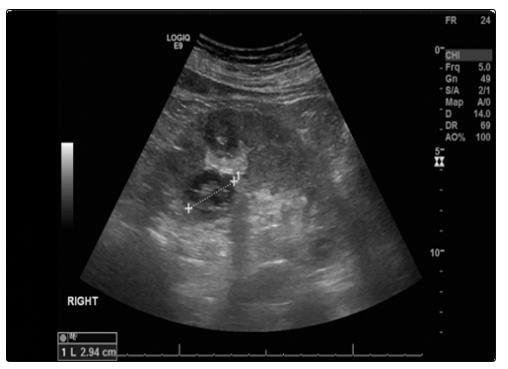

A previously healthy 47-year-old male was referred urgently to the renal department with a recent decline in kidney function, which was previously normal. Initial laboratory results revelated a creatinine of 183 umol/l, haemoglobin of 97 g/l and an MPO ANCA titre of > 221.9 iu/ml. When seen in the clinic he described reduced appetite, with 2 stone of weight loss over 1 month. His physical exam was unremarkable. Given his reduced renal function, he had an urgent renal biopsy which showed focal segmental necrotising glomerulonephritis with a single cellular crescent in keeping with ANCA associated vasculitis. However, two complex renal cysts were seen on ultrasound in his right kidney (Fig 1)and until malignancy was ruled out it was decided to treat with steroid monotherapy (prednisolone), not with cyclophosphamide. Initial response to this appeared to be effective, reducing creatinine from 214 to 126 umol/l.

Fig (1): Ultrasound with contrast right kidney showing 2 complex cysts located in the anterior cortex. There is a 3.5 cm cystic lesion with focal echogenic area measuring 1.8 cm. There is a second complex cyst measuring 3.5 cm close to the posterior mid renal cortical lip. This second cyst has a slightly irregular border and central echogenic complex septi.